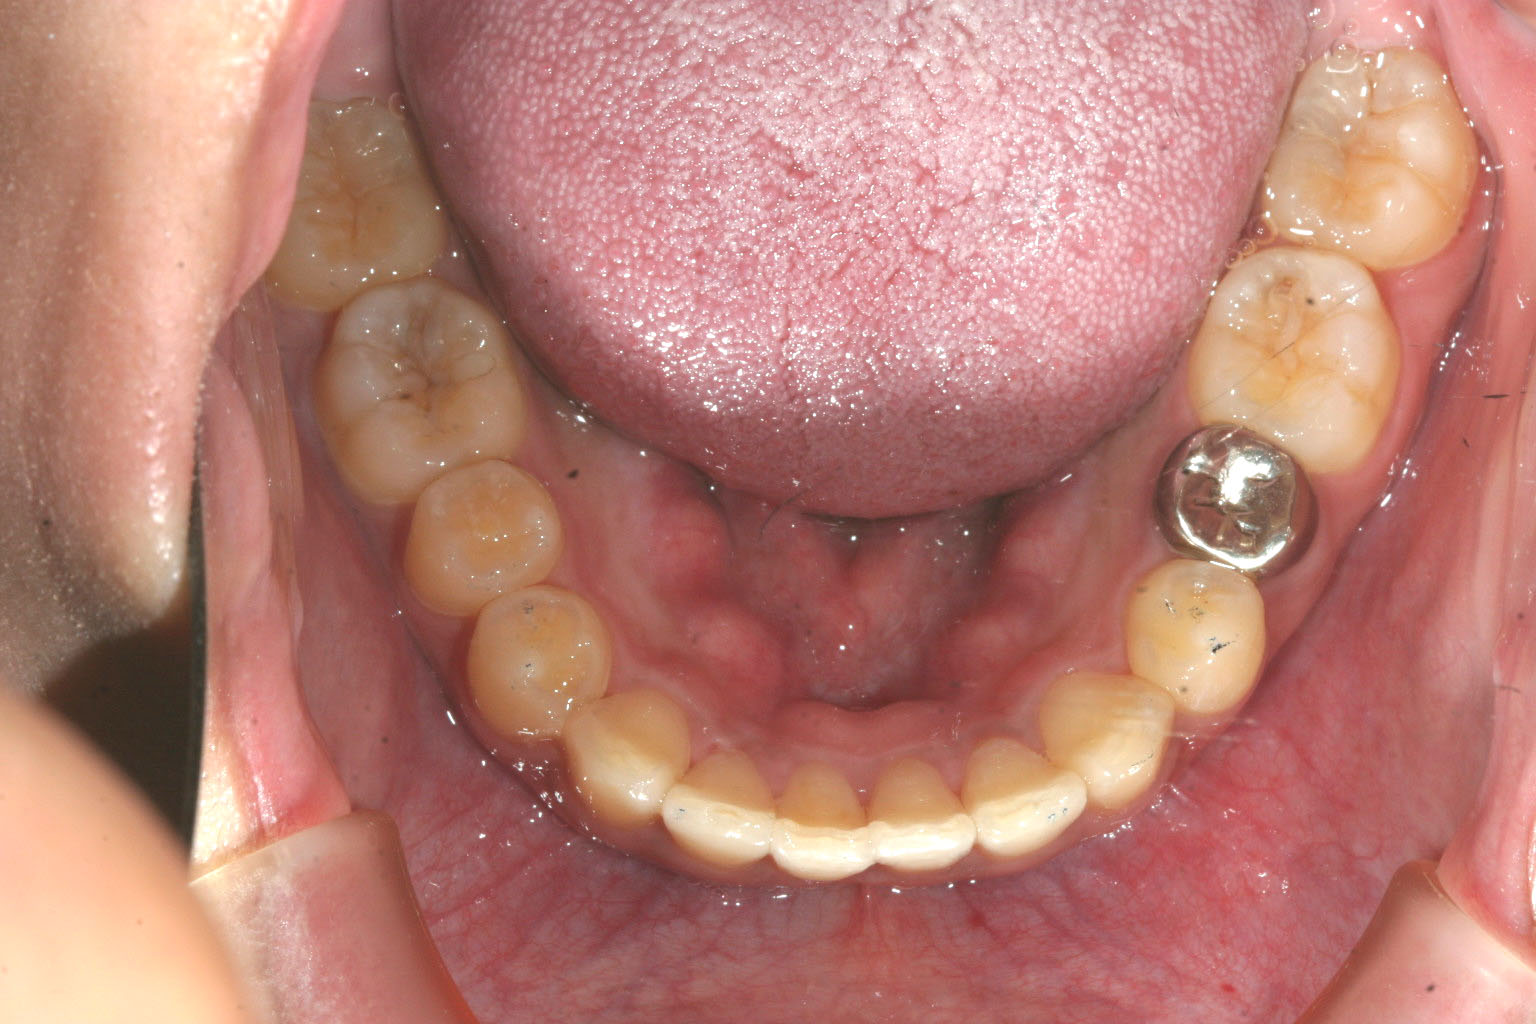

下顎も綺麗に改善しました。

前歯のねじれに関しましてはチューイーをしっかり噛む事により自動的に改善するような

設計にしてありました。

今回の患者様はこちらの指示に良く従って頂いたお陰で難なく短期間でこの様に綺麗な症例に仕上がりました。